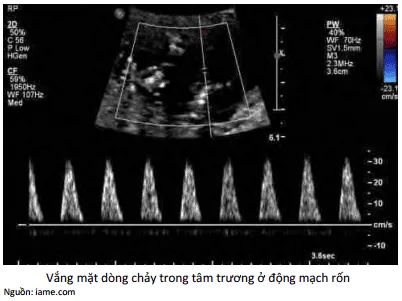

Trở kháng động mạch rốn tăng cao có thể dẫn đến mất dòng chảy cuối tâm trương hoặc đảo ngược dòng chảy cuối tâm trương. Khi xuất hiện giảm, mất hoặc đảo ngược dòng chảy cuối tâm trương trên Doppler động mạch rốn, cần đánh giá kỹ lâm sàng để quyết định chấm dứt thai kỳ hoặc theo dõi chặt chẽ.